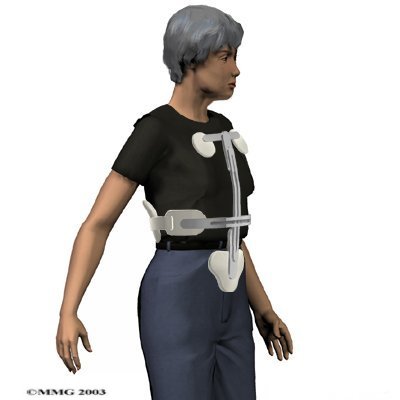

Most patients are fit with a special back brace, called an orthosis. This type of brace is molded to the patient's body. It limits spine movement in general, though the brace is usually fashioned to keep patients from bending forward. This protects the fractured vertebral body so it can heal and also assists with pain relief. Patients who wear a special brace will be advised to move about as normal but to limit strenuous activities, such as lifting and bending.